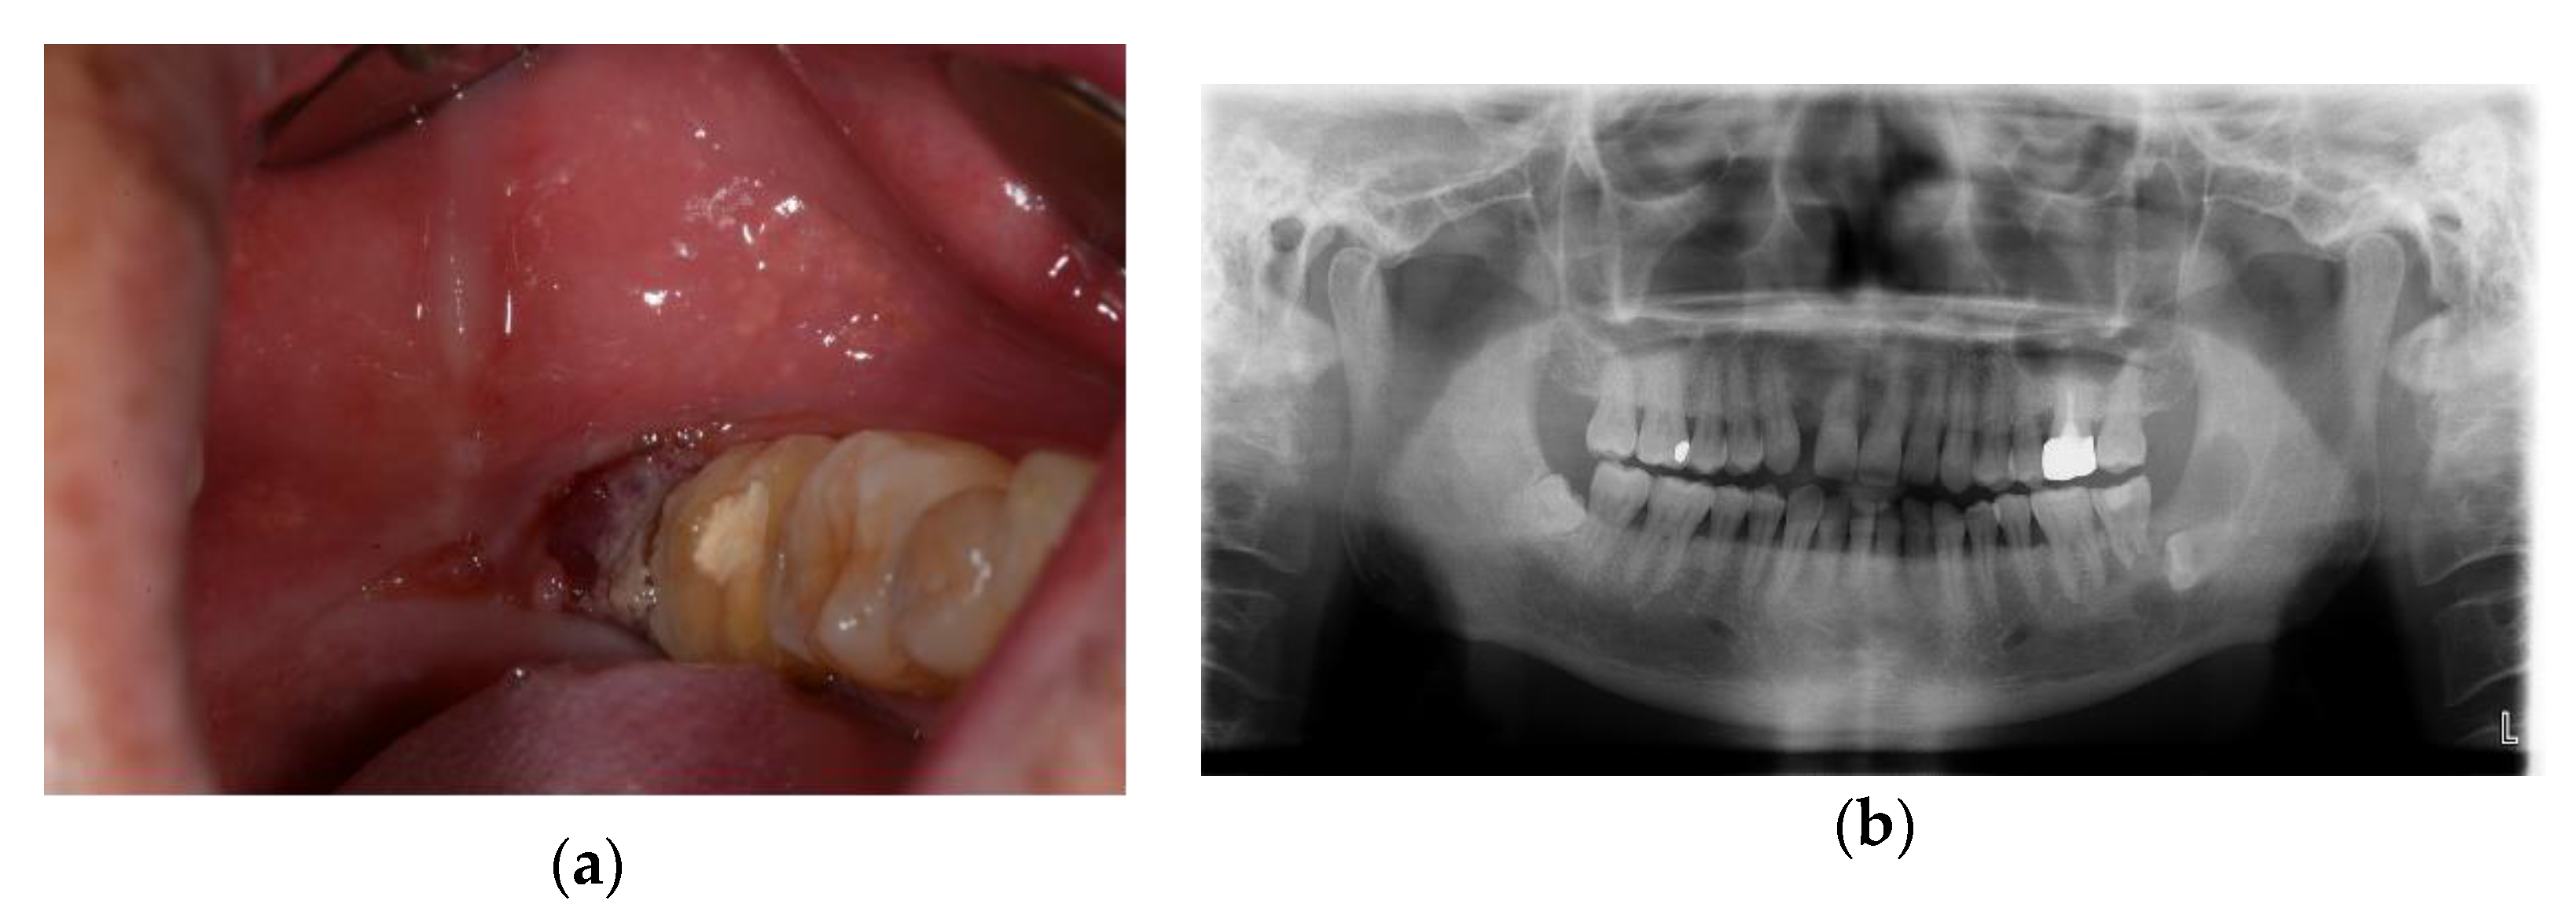

A 58-year-old male presented at the department of oral and maxillofacial surgery with an infection of the retromolar trigone area (Figure 5).

Figure 5.

Initial examinations: (a) intraoral photograph showed the granulomatous lesion on the left retromolar triangle; (b) panoramic view showed the impacted tooth and multilocular radiolucency lesion.

Incisional biopsy results diagnosed a plexiform type of ameloblastoma. Segmental mandibulectomy was planned for the management of the lesion, and a DCIA flap was planned to reconstruct the resected site.

Osteotomy was performed at the planned location using a pre-designed 3D-printed surgical guide. Bicortical DCIA flaps were harvested by applying a 3D-printed surgical guide to the external surface, and an internal oblique muscle was also harvested (Figure 6).

Figure 6.

Intraoperative photograph: (a) a resection guide was applied on the mandible; (b) iliac crest bone and internal oblique muscle flap were harvested using resection guide.

Micro-anastomosis with the facial artery and the facial vein was performed, and fixation was conducted with a titanium miniplate for the reconstruction of the mandible.

From 2 weeks postoperatively, the patient was complaining of pain in the donor site while walking. A radiograph of the pelvis was taken and the patient was diagnosed with an ASIS avulsion fracture.